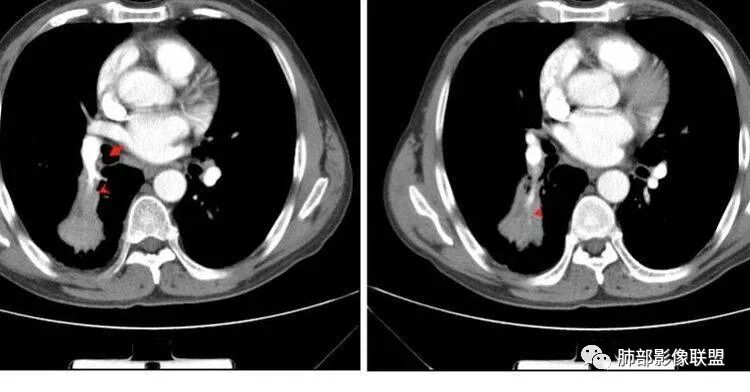

M-Imaging :病人胸痛20天,病灶三角形宽基底与胸膜贴近,肺门侧支气管通畅,造影显示肺动脉狭窄,考虑肺动脉栓塞,肺梗死?HeKate·Awizard·Sinitici:老师,请教一下,这是联盟讲座里说到的支气管爬行征吗?M-Imaging :我觉得像肺梗死,支气管通畅的采莲:中老年男性,右肺下叶背段片状影,边缘收缩平直,会不是异物可能么呢?中老年男性,咳嗽咳痰发热,急性起病,右肺下叶背段片状影,边缘收缩平直,周围有点片影,考虑异物合并感染,鳞癌待排。南边:多种意见:肺梗死、结核、异物、鳞癌肺动脉还好吧

南边:紧贴着斜裂过来的一个病灶,它的特点是:外围大,内带小。它整个下叶背段体积与对侧相比稍微缩小一点,但是缩小地不是很厉害。外支朝前下走了,仔细看血管,肺动脉走行自然,直达远端。远端实变区是肉芽肿成分,稍微有一点低密度,没有明显坏死,稍微有一点点坏死。而且附近有很多卫星灶,附近很多斑片影,有一些明显有气道壁增厚,细支气管炎的特点,还有就是下叶其他段很多斑片状影。换个角度,第一如果是肺癌,刚才看到PET-CT提示肺癌伴阻塞性肺炎,这个是不符合的。第二如果是肺癌阻塞性肺炎,近端血管肺动脉走行不会那么自然集聚的,这个是不符合的。理由是:如果这个病灶是肺癌,那么明显属于中央型肺癌,中央型肺癌的特点是近端大,远端小,近端是一个肿块,远端阻塞,远端阻塞是阻塞性炎症或者不张,它应该体积缩小,斑片状实变,不会这么密实。刚才有老师提到支气管,这个片有缺陷的地方,给的图像好像那层,如果把其他图像拿开再重叠一下。

如果是单纯看这幅图像,会觉得背段外侧支气管分支堵塞的,但是看下面这层图

南边:你就发现外侧支气管朝下走的分支非常自然,通畅的。

南边:这个肺门区,11区和7区都有一些淋巴结,淋巴结的形态不是类圆形,而是梭形的。这个病灶给的图比较少,个人倾向,第一强化非常均匀,肉芽肿性病变;第二,里面血管走行非常自然,远端大近端小,倾向炎性,特别是下面还有斑片状影,非阻塞远端,支气管远端病灶下叶背段,其他段也有,所以我倾向炎性;另外,它里面整个走行符合支气管树爬行征,我倾向结核可能,首先我定在炎性,其次有没有结核的可能。